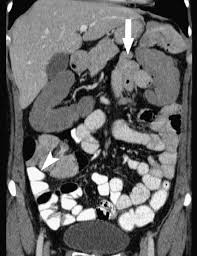

Coronal Plane Of Abdominal Mdct In A 54 Year Old Woman Prepared With Download Scientific Diagram